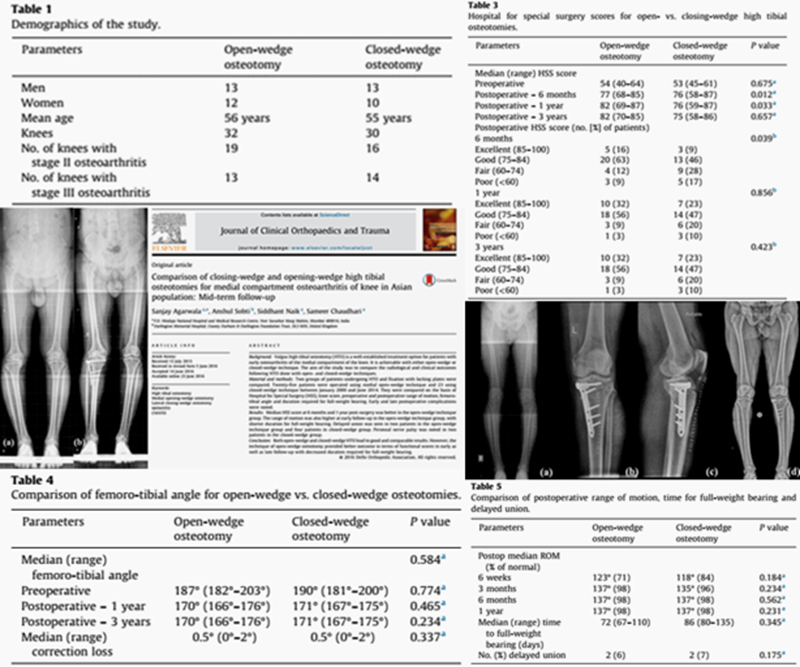

两种截骨对比 OWHTO VS CWHTO

OWHTO和CWHTO同样可获得良好临床疗效。但CWHTO存在腓总神经损伤的风险。

胫骨高位截骨术(OWHTO和CWHTO)通过截骨,改变下肢力线,延缓关节炎进展,适用于治疗伴有内翻畸形的膝关节内侧间室骨关节炎,两者截骨术式均可获得良好临床疗效。

CWHTO不需植骨,但矫正有限,需行腓骨截骨,容易损伤腓总神经,造成肢体短缩;

OWHTO不需腓骨截骨,不伤腓总神经,可早期功能锻炼,但骨缝大时往往需行植骨,不愈合率相对CWHTO高;